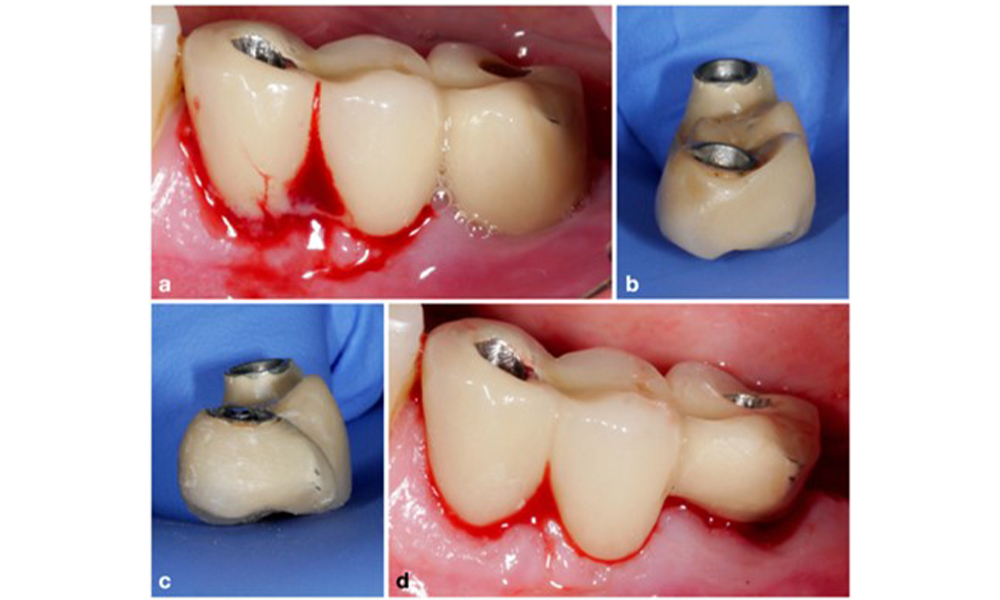

Étant donné que le principal facteur étiologique des complications biologiques péri-implantaires est le biofilm buccal, deux aspects cruciaux doivent toujours être considérés comme faisant partie intégrante du traitement, indépendamment d'un diagnostic de mucosite péri-implantaire ou de péri-implantite : (1) le niveau d'hygiène buccale et (2) la nettoyabilité de la restauration prothétique (figure 4).

Ainsi, les habitudes d'hygiène bucco-dentaire du patient, la conception de la restauration prothétique et le positionnement de l'implant doivent favoriser un nettoyage efficace. Si nécessaire, des ajustements de la restauration existante (figure 5) et des instructions spécifiques pour des mesures d'hygiène bucco-dentaire adaptées sont essentiels (figure 6) (Hamilton et al. 2023 ; Jepsen et al. 2015).